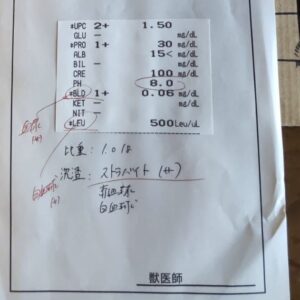

くるみちゃんの膀胱結石定期検査報告

結石は 型が薄くなっているのでは?と 血尿や残尿感 膀胱炎が悪化しないように 引き続き 栄養と膀胱粘膜管理 尿の検査を頑張ってもらってます。